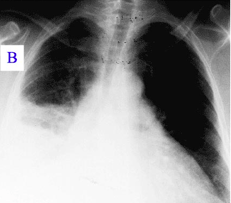

Otprilike polovina zaraženih osoba ne pokazuje simptome. Tokom svog razvoja bolest može preći u atipičnu upalu pluća, što može rezultirati akutnim respiratornim distres sindromom opasnim po život, pri čemu se takvi simptomi obično javljaju u prva četiri do pet dana infekcije.

Problemi sa plućima - neki ljudi koji imaju Q groznicu razvijaju upalu pluća. To može dovesti do akutnog respiratornog distresa.